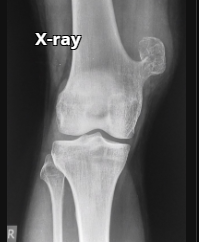

Fratura do platô tibial lateral - Schatzker tipo 2 (traço de fratura + depressão do plato lateral).